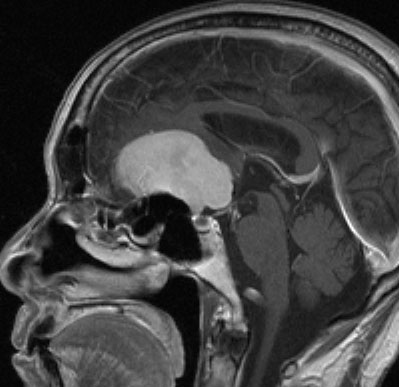

30代の女性に発生した髄膜腫です,一見すると松果体細胞腫と見分けはつきません。右の画像に見られるように典型的な中脳水道狭窄を生じていました。

軽度の閉塞性水頭症もありますが,頭痛も無く無症状なので経過を観察しました。髄膜腫だと診断できるのは,右の画像で見られるようにガレン大静脈が右側に偏っているからです。松果体細胞腫の場合は,ガレン大静脈は上方に変位します。

1年間経過観察したら水頭症が進行して脳室が拡大,腫瘍のサイズも大きくなりました。右側の画像で見られるようにガレン大静脈の左側のテントの下面から発生した髄膜腫でした。

左は手術直後の画像です,手術は左側のテント下面を見るために,後頭部経テント法 OTA occipital transtentorial approach で,小脳テントの左側を切断して腫瘍を全摘出しました。右側は6年後の画像ですが,腫瘍再発はありません。